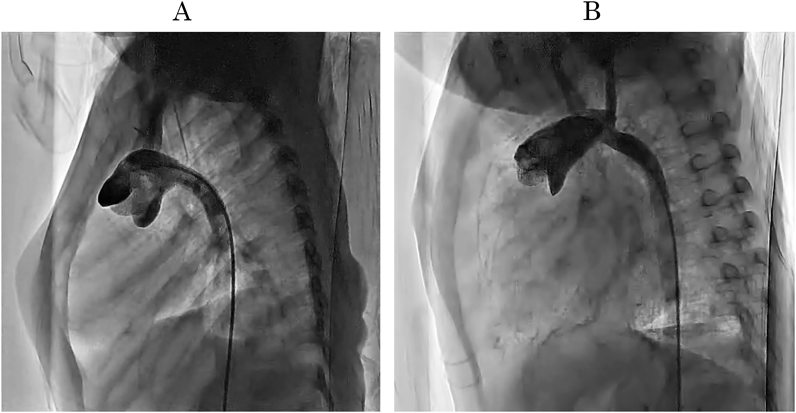

Fig. 2 (A)従来の自己組織のみによる大動脈再建.(B)肺動脈幹温存法による大動脈再建:従来の方法に比べて新上行大動脈が長く,大動脈弓の角度が緩やかである

大動脈再建

大動脈再建に際して,広い流路を確保する必要があり,新大動脈での狭窄(CoA残存)は後負荷増大とそれによる肺血流増加によって術後心不全の要因となる.20 mmHg以上の圧較差は治療対象となる4, 5).一方,拡大した大動脈も瘤化や大動脈後面の肺動脈圧迫を来すため注意が必要である.大動脈再建方法はNorwoodが自己組織のみによる再建とPTFEパッチ補填の両方を報告していたが2, 6),その後広い流路を無理なく確保するために組織補填を行うことが主流となった.欧米ではホモグラフトの使用が多いが,異種心膜や自己心膜,またゴアテックスなど人工物補填の報告もある7, 8).これらは成長性や石灰化などに課題があり,ホモグラフトも例外ではなく本邦では入手性でも劣っている.1995年にMee9)が自己組織のみの再建を報告しているが,同様に本邦では自己組織を主体とした再建が主流となっている.同方法での問題点として新上行大動脈(主肺動脈)が短く,肺動脈弁から大動脈弓までの長軸方向距離が短いのみでなく,上行大動脈と下行大動脈間(いわゆるretro aortic space)の狭小化がある.これらの解決として小沼10, 11)が肺動脈幹温存法,山岸12)がChimney法として長軸方向への新上行大動脈の長軸方向延長および短軸方向への縮小をすることでretro aortic spaceすなわち左肺門を開大し肺動脈狭窄や気管支狭窄を生じにくい大動脈形態となる再建法を報告した(Fig. 1).また大動脈弓の形態も従来の再建法での鋭角な大動脈弓角度がより緩やかになり,壁せん断応力とエネルギー損失の減少と心仕事量の軽減も期待される(Fig. 213).自己組織のみによる再建によってもホモグラフトをはじめとする補填手術と同等の手術成績が得られることが期待されている.また上行大動脈の再建において冠動脈灌流はNorwood手術の最も重要な部分である.上行大動脈の直径が小さい場合(1~3 mm)は大動脈基部で隣接する主肺動脈に吻合すること多いが,この領域でわずかな歪みがあると冠還流に影響する.個々の大動脈の形態に応じて側々吻合や離断しての端側吻合などを行う.また冠動脈起始異常を稀に合併する場合があり,これらの異常はすべて大動脈弁閉鎖症例において報告されており,手術に影響を及ぼす可能性がある.最近の剖検研究では22%に冠動脈の異常があり,それが患者の死亡と関連していた14).左冠動脈が肺動脈分枝から起始している症例の場合,冠動脈移植もしくは肺動脈幹温存法が必要となる15, 16).下行大動脈吻合時にinterdigitating法(Fig. 3)として下行大動脈を縦切開することで良好な成績の報告もある17)